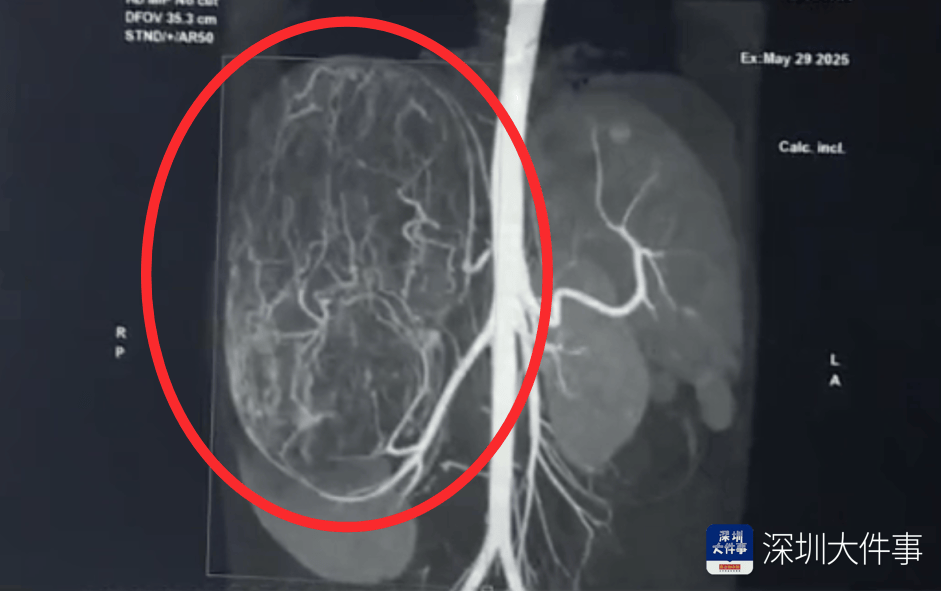

影像检查结果出来,所有人都倒吸一口冷气:一个直径27厘米(比篮球还大)的巨型肿瘤,霸占了整个腹腔右半边。肝脏被它硬生生挤到了肚脐眼以下的位置!

5月30日,医生为婷婷做手术,打开腹腔后,医生遇到了挑战:婷婷的肾动脉异于常人:正常人就1根肾动脉供血,她居然有3根。还有一支来自腹腔干动脉,一支来自腰动脉。

这三根“命脉”就盘踞在巨大的瘤体上,稍有不慎,剪错一根,就可能引发大出血。

手术团队屏气凝神,抽丝剥茧,一根一根精准找到、小心分离、稳稳阻断……经过3个多小时的精密操作:重达2.43公斤直径达27厘米的“巨无霸”肿瘤被完整端出。周围需要清扫的淋巴和脂肪组织也被清除。

术后病理结果显示,婷婷腹中肿瘤是肾嗜酸性细胞瘤,且为良性。意味着根治性切除后,婷婷预后会非常好。